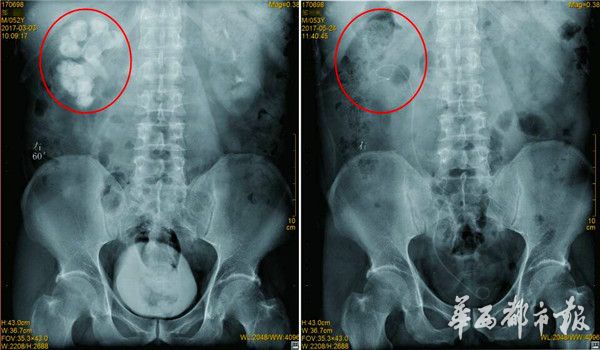

今年3月和5月,邹先生先后做了5次手术。这是术前和术后对比图。

今年春节后,不堪忍受的邹平终于下定决心与结石“战斗”到底,决定到成都治疗,专家检查后发现,病人右肾的肾盏、肾盂都布满了结石,“肾脏里的所有空间都被结石堵死了,长端达到了10厘米,同时右肾功能也仅剩2成左右。”

因为病人右肾结石巨大,四川结石病医院泌尿一科结窦医平主任建议实施高难度的多通道3镜联合分期手术,将右肾结石全部取出。随即,今年3月,医生相继为其完成了三次手术,等到病人病情达到理想状态后,今年5月又完成了两次手术,才将病人右肾内的巨大结石粉碎并清除。目前,邹先生即将康复出院。